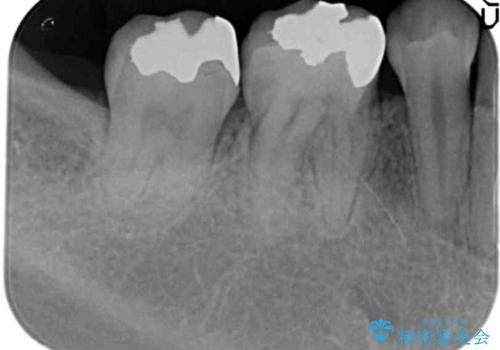

- 矯正治療終了後、前々から気になっていた笑った時に見える銀歯を白くしたいと希望され来院されました。

銀歯を拡大鏡下で丁寧に除去したのち、小さな虫歯も除去し精密で適合の良いセラミックインレーによる再修復を行います。